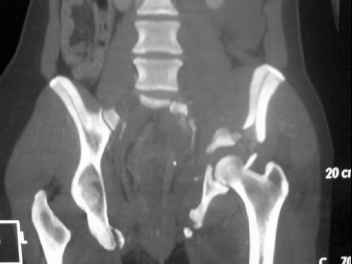

41 yo female , fall from 10 meters five days ago. Hemodynamically unstable on admission treated by angio and embolization and skeletal traction, with no external support. No associated injuries.

Based on CT scan the pt has a both column fracture with conminuted dome and displaced anterior column and a sacral Denis 1 fracture with a displaced left ala. I think the best approach for the acetabular fracture is ilioinguinal with Smith-Petersen extension but don't know exactly the sequence . Will you start with the sacral fracture? Which technique?